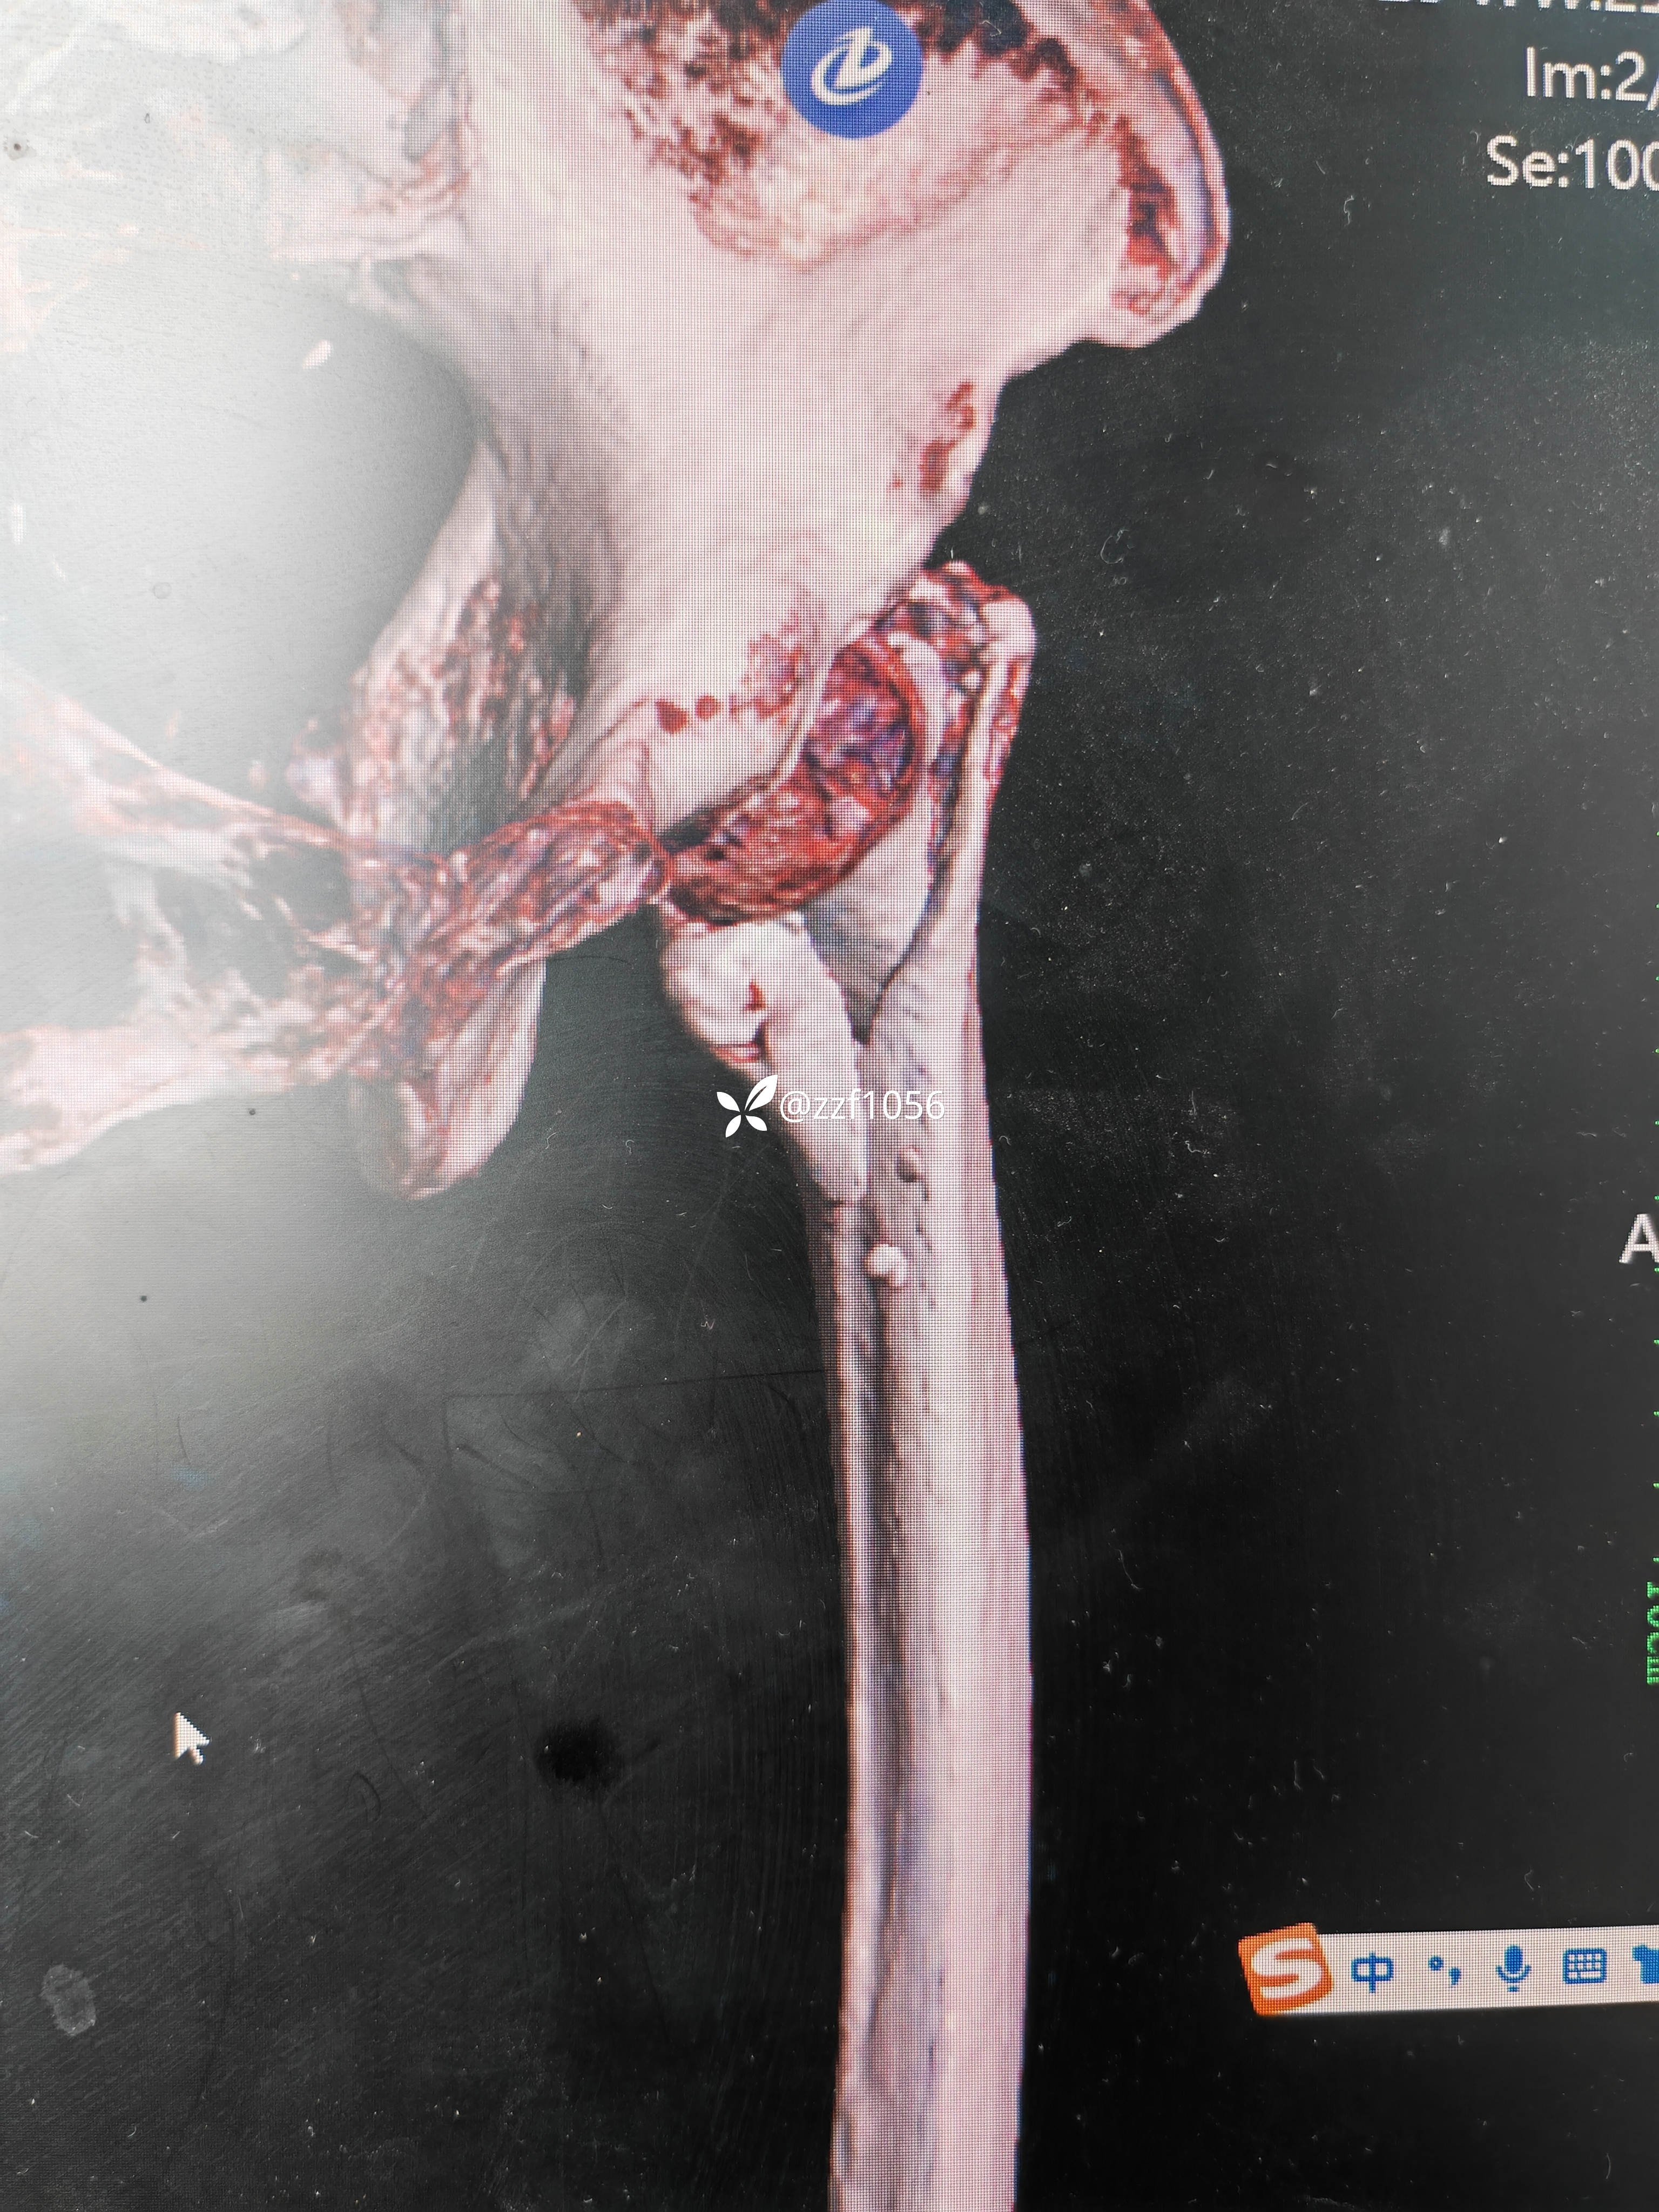

行走三个月康复良好,奈何再次摔伤,导致左侧转子间再骨折,A2.3型